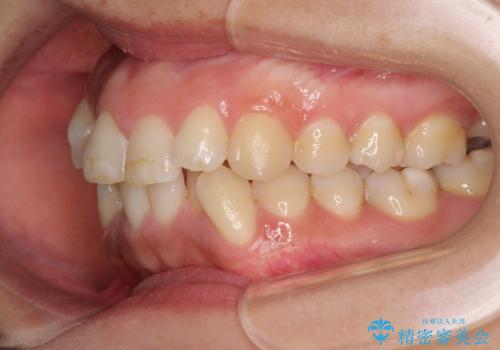

- 上下前歯のデコボコを気にして来院された患者様です。

デコボコが強いため、非抜歯で矯正をすると出っ歯仕上がりとなるため、上下左右の第一小臼歯4本を抜歯することとしました。